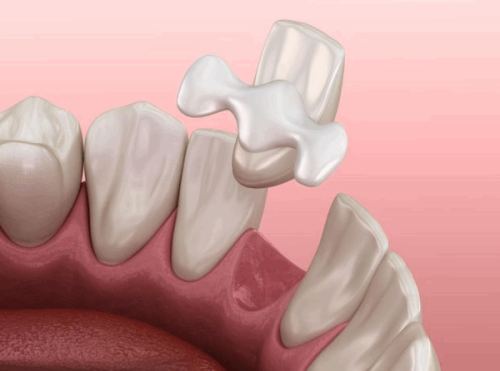

种植牙是全博口腔的重点项目之一。在种植牙领域,全博口腔有着一定的优势。

从技术上来说,医生团队能够运用现代化的设备和技术,为患者提供科学有效的种植牙方案。在术前,医生会进行详细的检查和评估,根据患者的口腔情况和需求,选择合适的种植体和种植方案。在术中,凭借丰富的经验和不错的技术,确保种植手术的顺利进行。